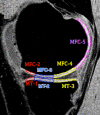

Purpose: To longitudinally evaluate cartilage matrix changes by using magnetic resonance (MR) imaging T1(ρ) (T1 relaxation time in rotating frame) and T2 quantification and to study the relationship between meniscal damage and cartilage degeneration in anterior cruciate ligament (ACL)-reconstructed knees.

Materials and methods: This was an institutional review board-approved, HIPAA-compliant study. Informed consent was obtained. Twelve patients with acute ACL injuries were imaged with 3.0-T MR imaging at baseline (after injury and prior to ACL reconstruction) and 1 year after ACL reconstruction. Ten age-matched healthy subjects were studied as controls. Cartilage T1(ρ) and T2 were quantified in full thickness, superficial, and deep layers of defined subcompartments at baseline and follow-up in ACL-injured knees and were compared with measures acquired in matched regions of control knees. Meniscal lesions were graded by using modified subscores of the Whole-Organ Magnetic Resonance Imaging Score system.

Results: T1(ρ) values of the posterolateral tibial cartilage in ACL-injured knees were significantly elevated at baseline compared with T1(ρ)values of control knees and were not fully recovered at 1-year follow-up. T1(ρ) values of weight-bearing medial femorotibial cartilage in ACL-injured knees were significantly elevated at 1-year follow-up compared with those of control knees. No significant differences in T2 values between ACL-injured and control knees were found. Patients with lesions in the posterior horn of the medial meniscus showed a greater increase of T1(ρ) and T2 from baseline to follow-up in adjacent cartilage than patients without lesions in the medial meniscus.

Conclusion: Quantitative MR imaging T1(ρ) and T2 enable detection of changes in the cartilage matrix of ACL-reconstructed knees as early as 1 year after ACL reconstruction.